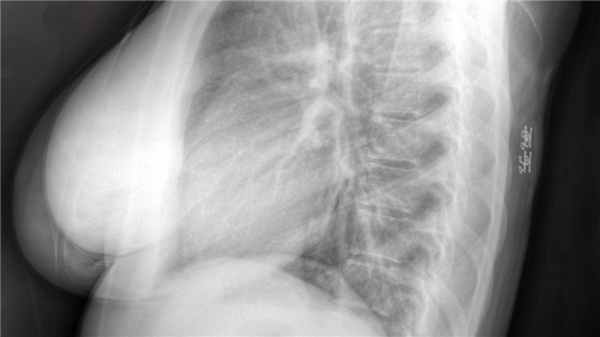

Больная П., 2 года, поступила в клинику СПбГПМУ с кифотической деформацией поясничного отдела позвоночника. При рождении обнаружены гемангиома поясничной области, дермальный синус. При обследовании выявлен порок развития позвоночника и спинного мозга — диастематомиелия, фибролипома терминальной нити. Ранее оперирована: в возрасте 3 месяцев были удалены костная перегородка позвоночного канала и фибро-липома терминальной нити. В дальнейшем отмечена прогрессия кифотической деформации. Ходит с 12 месяцев. При неврологическом осмотре обращает на себя внимание нижний парапарез (больше справа; Frankel D). Нарушений функции тазовых органов нет. По данным компьютерной томографии деформация позвоночника обусловлена множественными пороками развития нижнегрудного, поясничного и крестцового отделов позвоночника. На уровне Th1-Th7 тела позвонков грудного отдела сформированы типично, нарушена сегментация задних структур. Ниже уровня Th7 счет позвонков затруднен, имеют место множественные дефекты формирования, слияния и сегментации тел позвонков, задние структуры расщеплены. Обращает на себя внимание полный поперечный дефект передних структур на уровне условной середины поясничного отдела позвоночника (рис. 1).

Рис. 1. Предоперационная компьютерная томография: a — множественные дефекты формирования, слияния и сегментации тел позвонков (вид спереди); b — полный поперечный дефект передних структур на уровне условной середины поясничного отдела (вид слева); c — расщепление задних структур нижнегрудного и поясничного отделов (вид сзади)